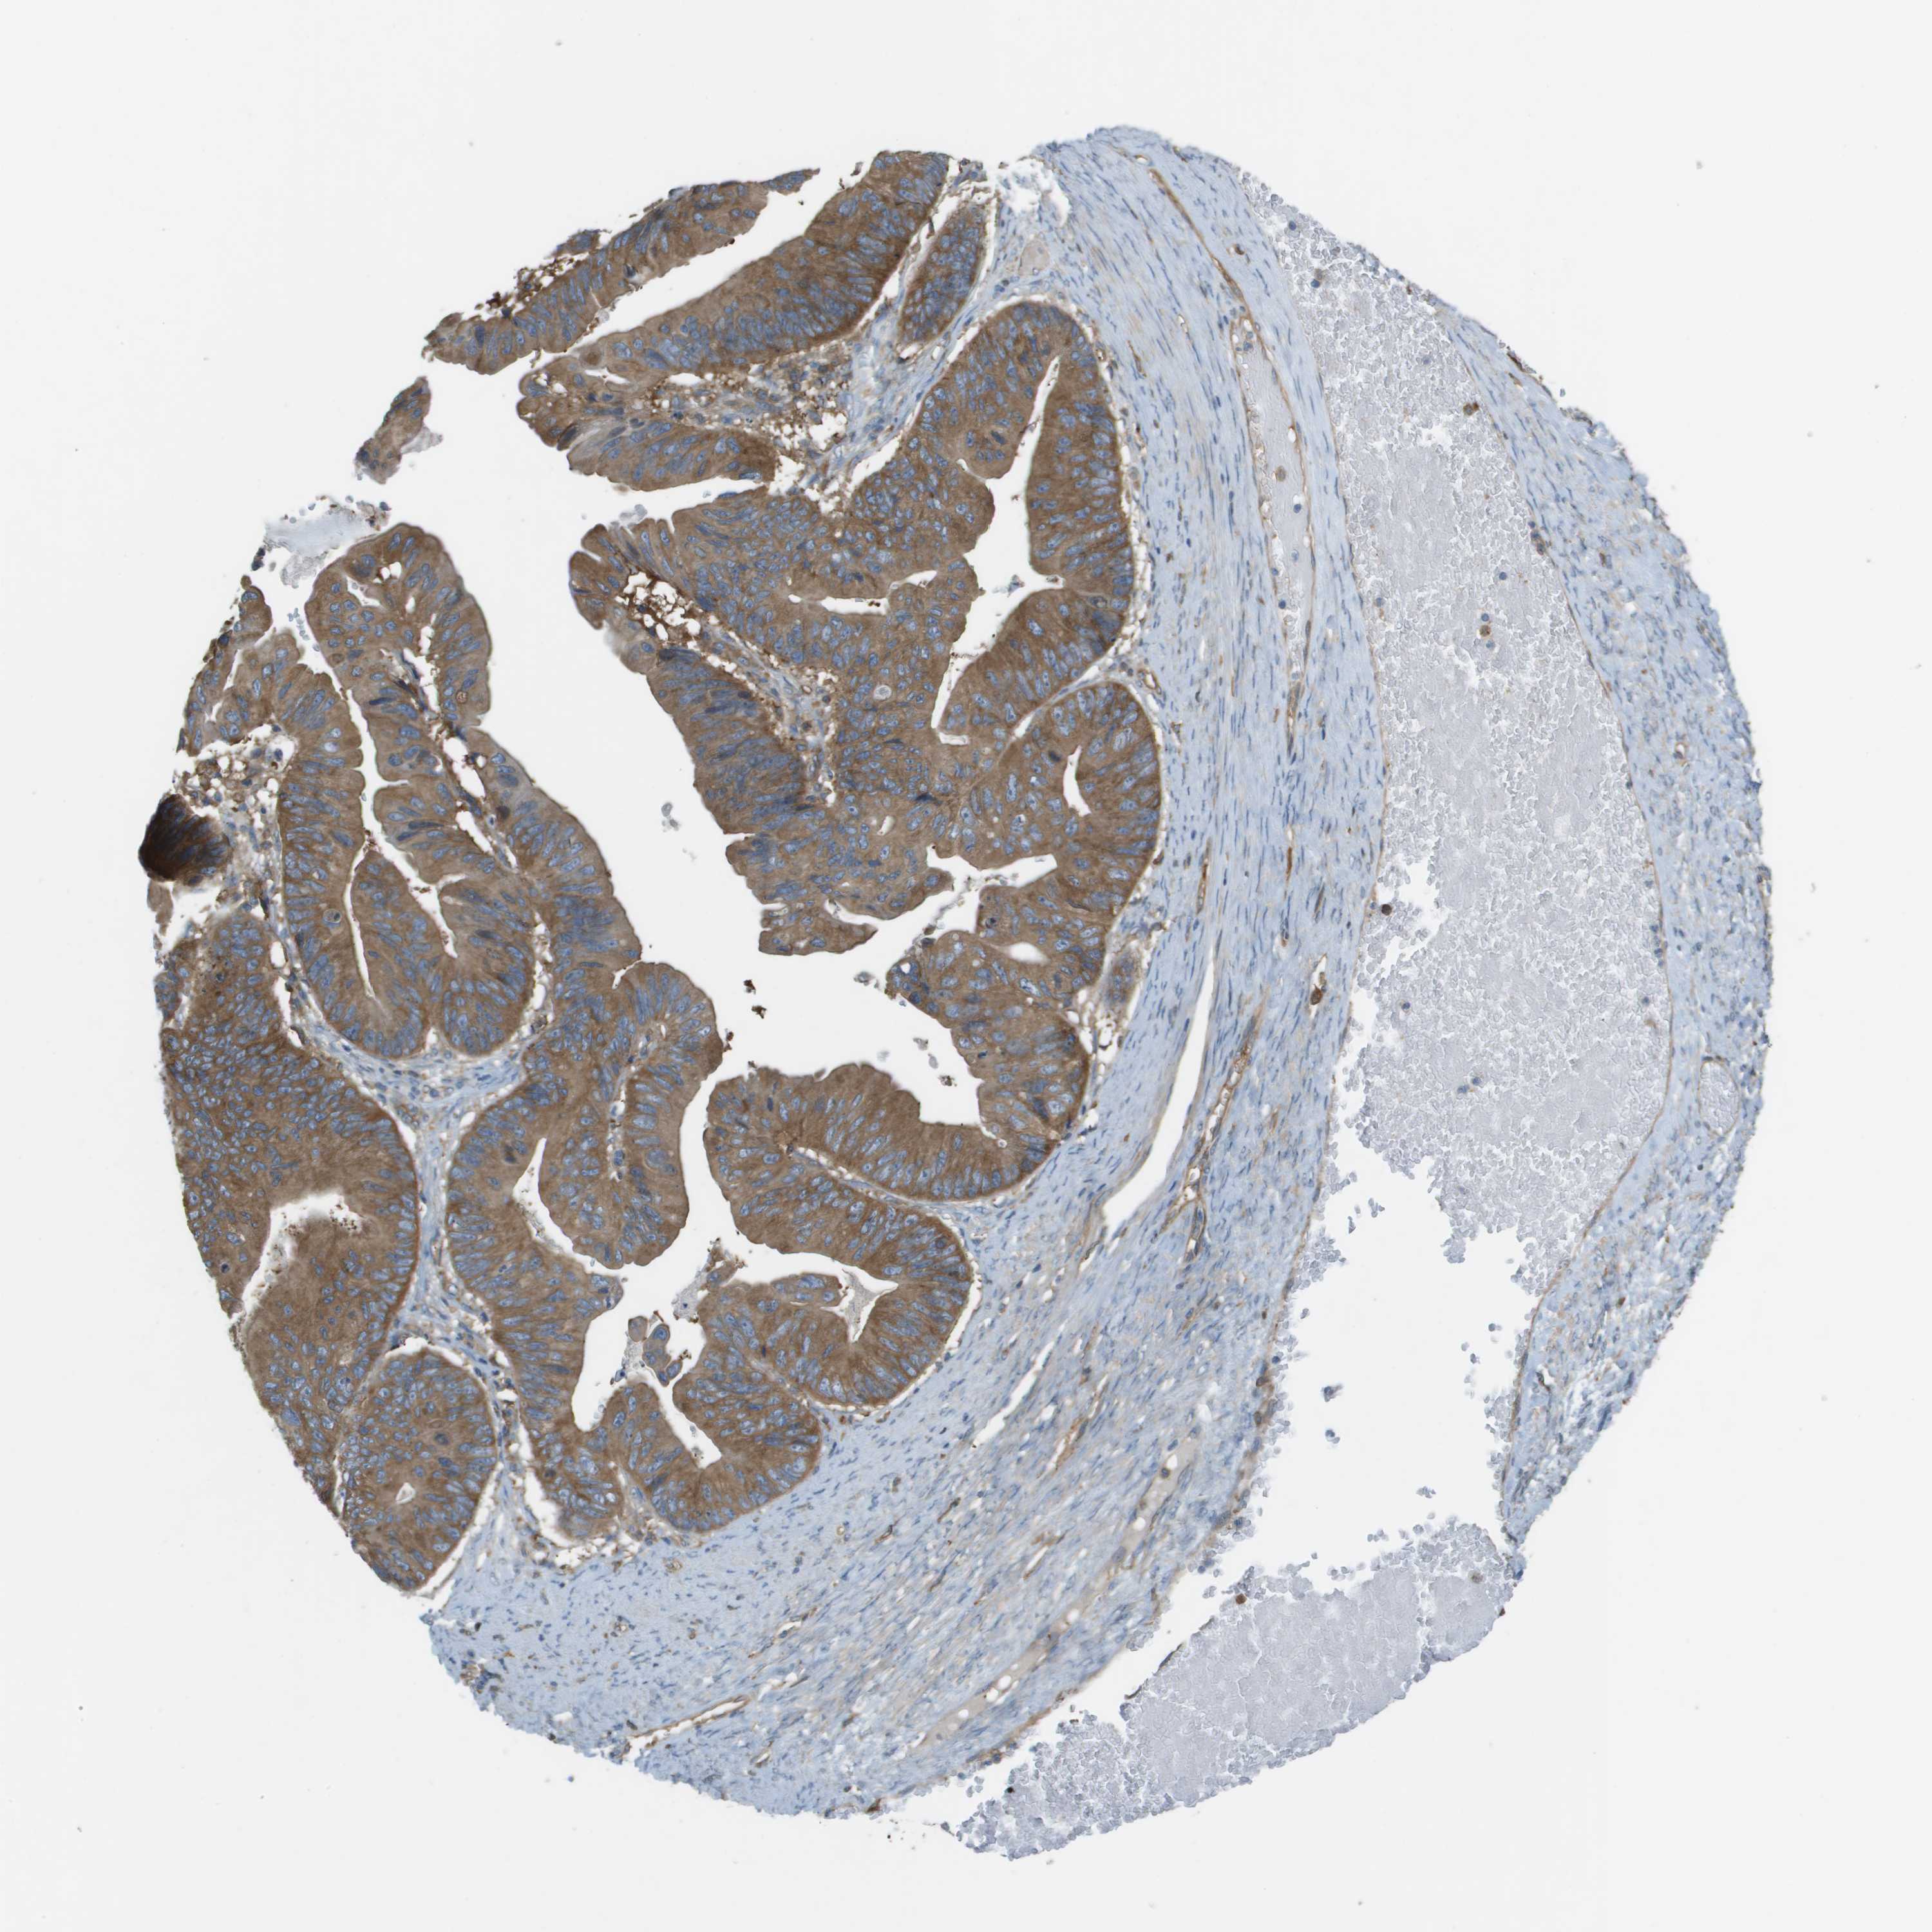

OVARIAN CANCER - Protein expressioni

A mouse-over function shows sample information and annotation data. Click on an image to view it in a full screen mode. Samples can be filtered based on level of antibody staining by selecting one or several of the following categories: high, medium, low and not detected. The assay and annotation is described here.

Note that samples used for immunohistochemistry by the Human Protein Atlas do not correspond to samples in the TCGA dataset.

Antibody stainingi

Antibody staining in the annotated cell types in the current human tissue is reported as not detected, low, medium, or high, based on conventional immunohistochemistry profiling in selected tissues. This score is based on the combination of the staining intensity and fraction of stained cells.

Each image is clickable and will lead to virtual microscopy that enables deeper exploration of all samples and also displays staining intensity scores, fraction scores and subcellular localization as well as patient and tissue information for each sample.

Antibody HPA070456

Antibody CAB017616

Staining

High

Medium

Low

Not detected

Intensity

Strong

Moderate

Weak

Negative

Quantity

>75%

75%-25%

<25%

None

Location

Nuclear

Cytoplasmic/membranous

Cytoplasmic/membranous,nuclear

Cystadenocarcinoma, serous, NOS

Cystadenocarcinoma, mucinous, NOS

Carcinoma, endometroid

Carcinoma, NOS